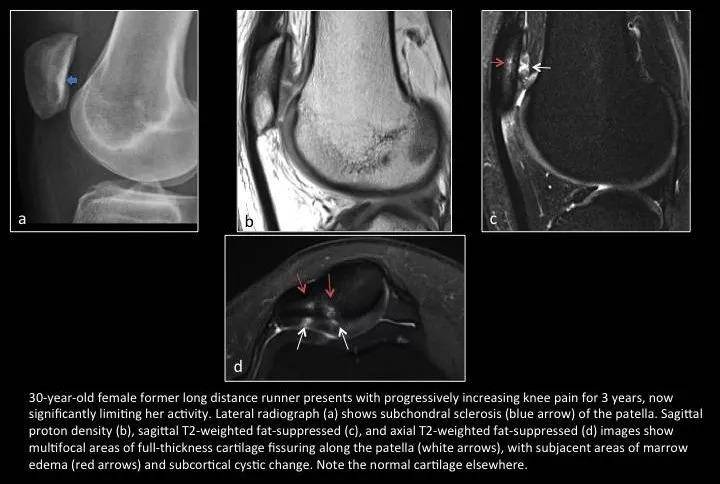

Fig. 12:Chondromalacia patellae

图12:髌骨软化症

女,30岁,长跑运动员,进行性膝关节疼痛3年;运动受限就诊。

a图蓝箭示髌骨软骨下骨质硬化;b,c,d图示多发局灶性全层软骨裂隙伴相软骨下骨髓水肿和皮质下囊变。